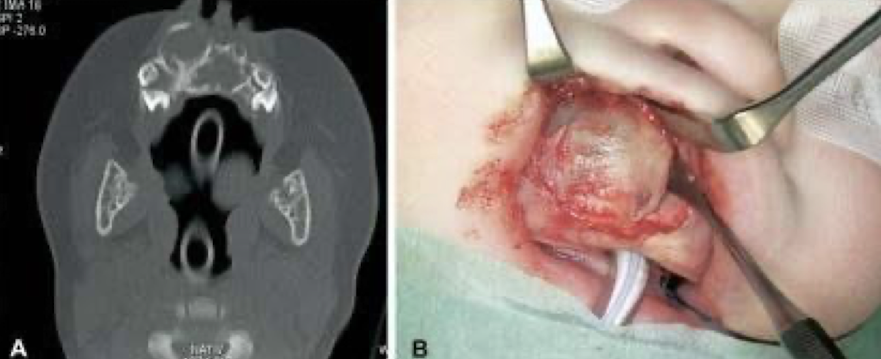

Krompecher in 1918 as a congenital "melanocarcinoma”

90% in head and neck and within the first 6 months of life

Male predilection (1.5:1), 60% on the palatal mucosa

Brownish-red mass of alveolar mucosa

High levels of vanillylmandelic acid in urine

BRAF V600E mutation identified in some cases (targeted therapies yay!)

surgically excised

MNTI

surgical resection (~20% recurrence rate; some intentionally left to be removed later)